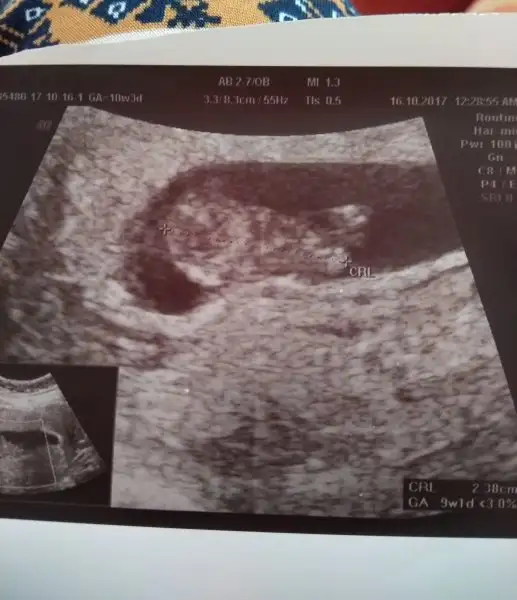

Teyzoslar yorumlayabilecekmisiniz bakalım bebeğimi

Eklentiler

• IMG_20171016_120129~2.webp

IMG_20171016_120129~2.webp

18,8 KB · Görüntüleme: 81